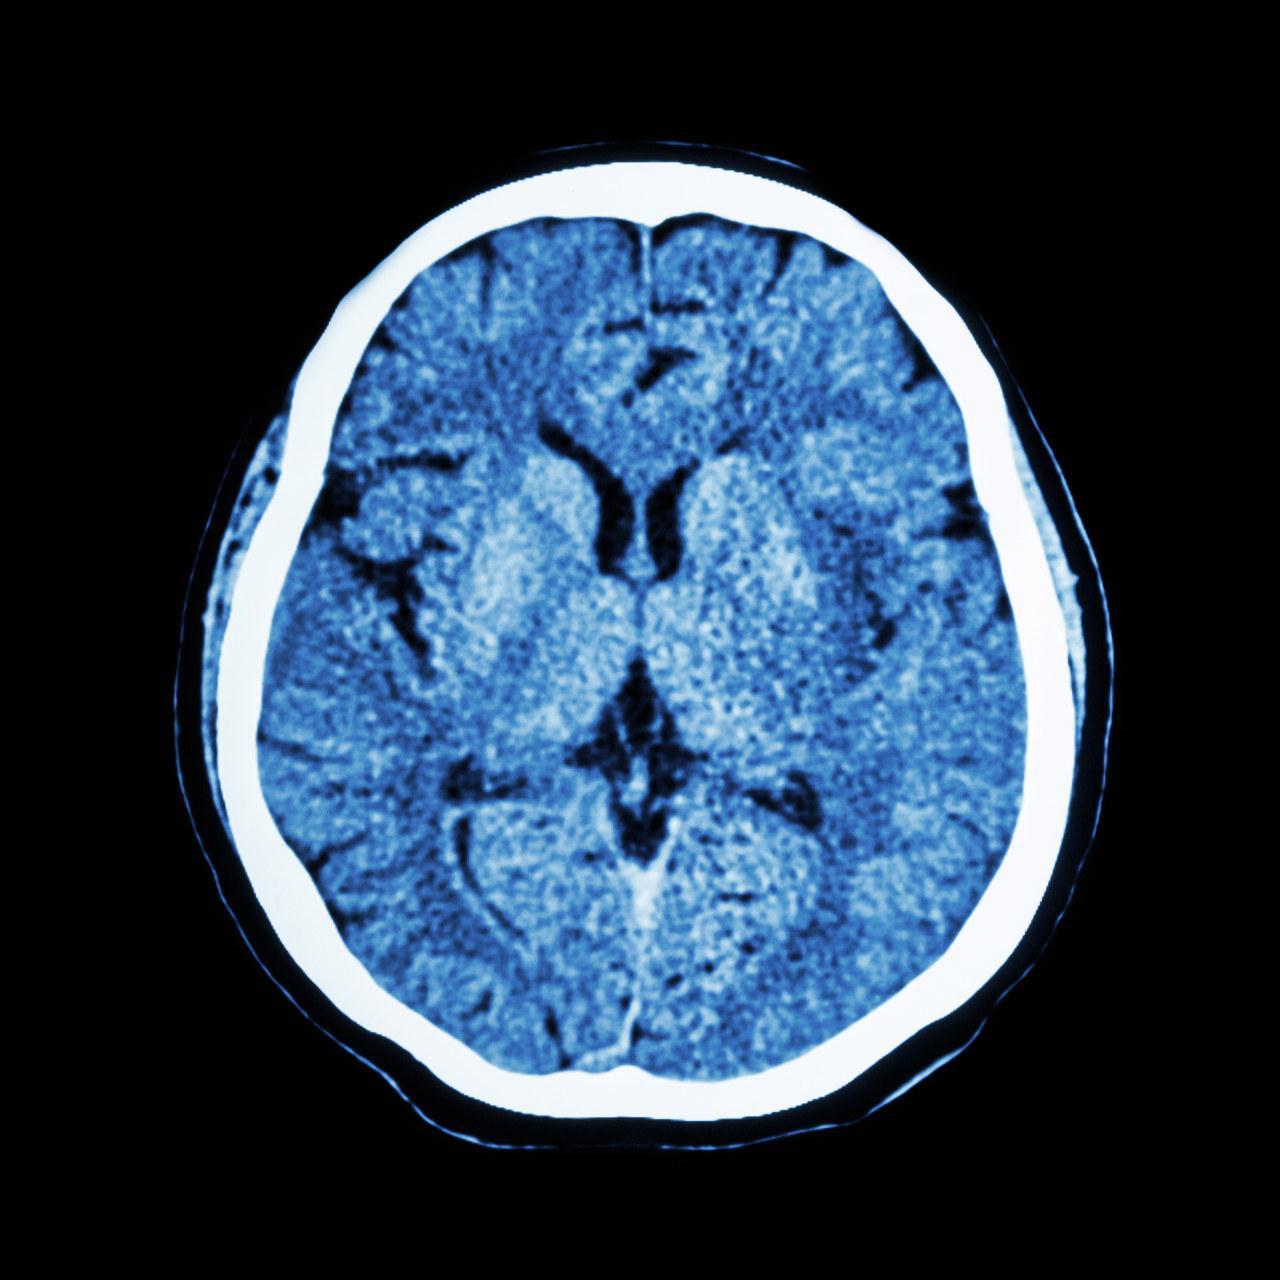

5、大腦

大腦如果不“乾淨”,可能會患上阿爾茲海默病。如今,很多老人可能會患有阿爾茲海默病,俗稱“老年癡呆症“,發病機制是大腦中β-澱粉樣蛋白斑塊沉積,以及細胞內過度碳酸化的Tau蛋白蓄積而成的神經纖維纏結。

5、 大腦幹淨——避免熬夜、堅持運動

白天大腦工作時,會產生“垃圾廢物”,比如Tau蛋白、β-澱粉樣蛋白,這些物質與老年癡呆有相關性。

而睡眠時,大腦會分泌腦脊液,清理這些“垃圾”。建議早點睡覺,儘量不熬夜,給大腦充足的“恢復”時間;堅持長期的規律中高強度運動可以增強心血管技能,進而淨化大腦。